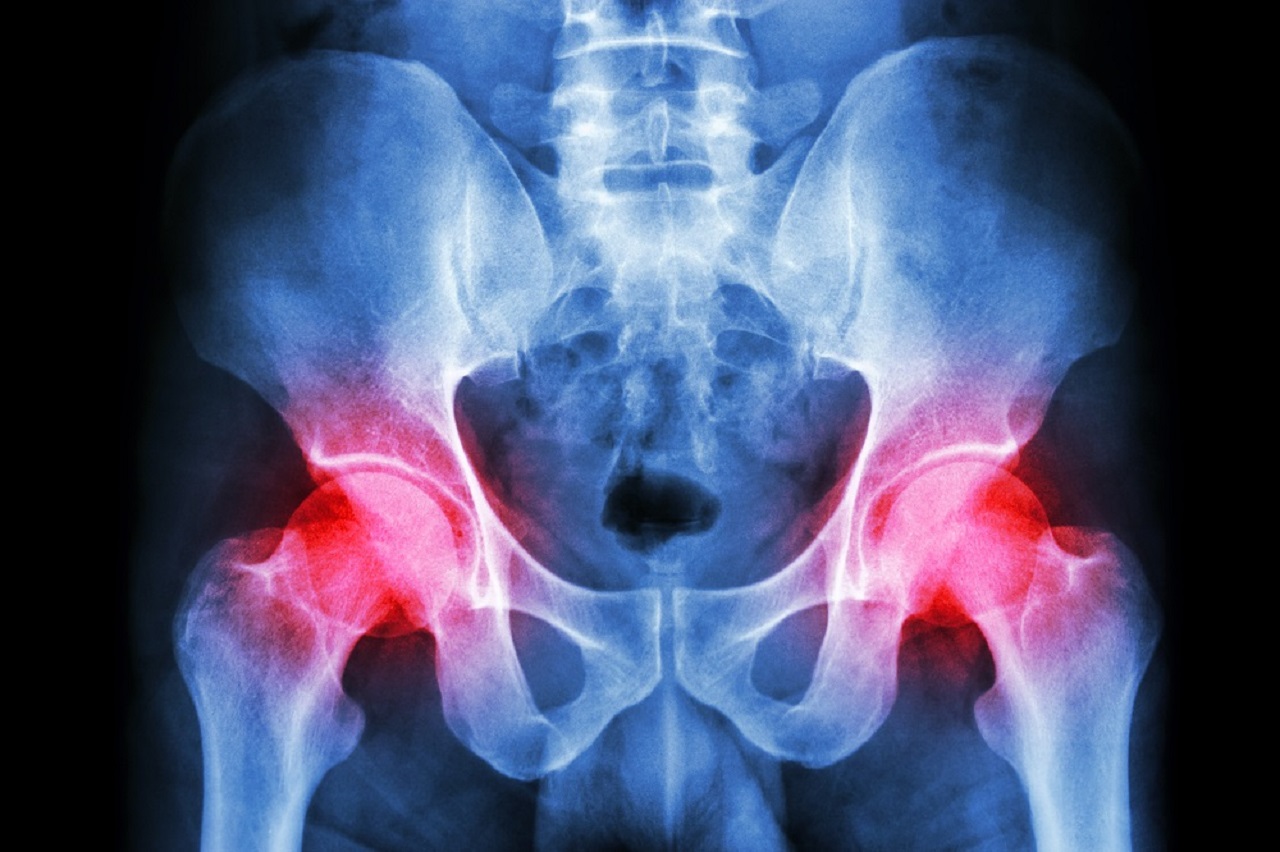

The hip joint is a large ball and socket joint built for stability. The ball is enclosed by a deep bony socket, which is further deepened by thick cartilage which surrounds its edges. There are many conditions of the hip joint and its surrounding structures which can cause pain and restriction, including the cartilage, the surrounding ligaments and muscles, and even the bone itself. The area of pain often gives us a clue as to the possible structures at fault, and whether they are due to the hip, its surrounding structures, or even referred from another body area such as the lower back. Below lists the different areas of pain and the possible structures at fault. Although this is not an exhaustive list, it does outline the more common conditions seen in the clinic.

• Osteoarthritis of the hip: degeneration of the cartilage which lines the bones in the joint